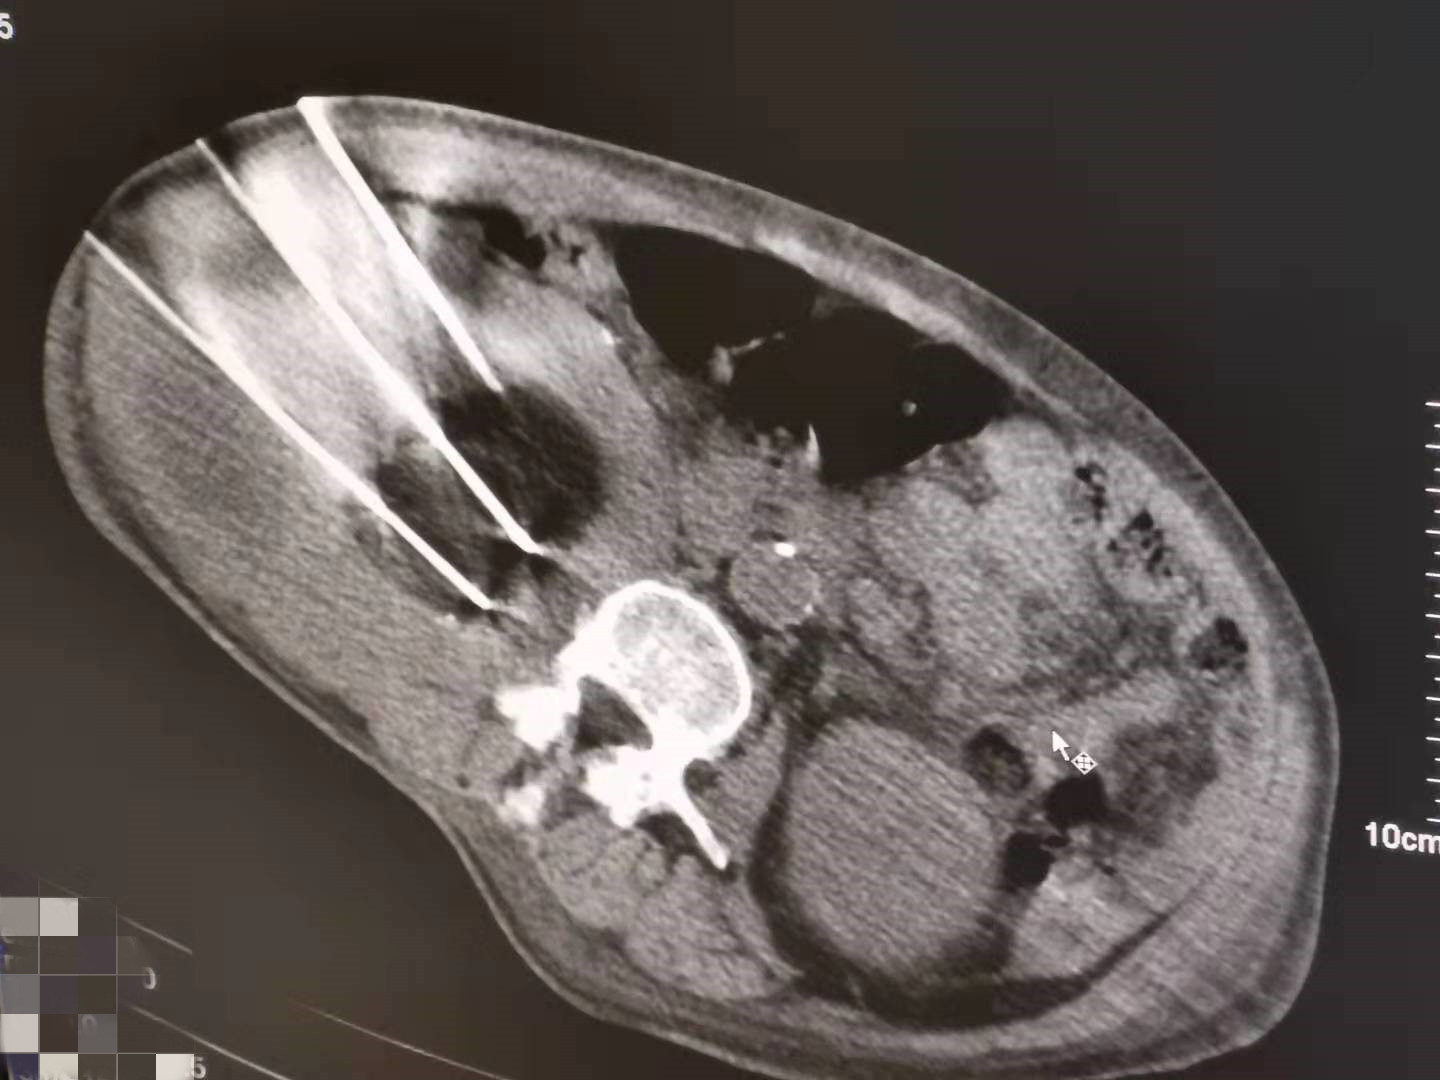

2021年5月份肾部氩氦刀手术